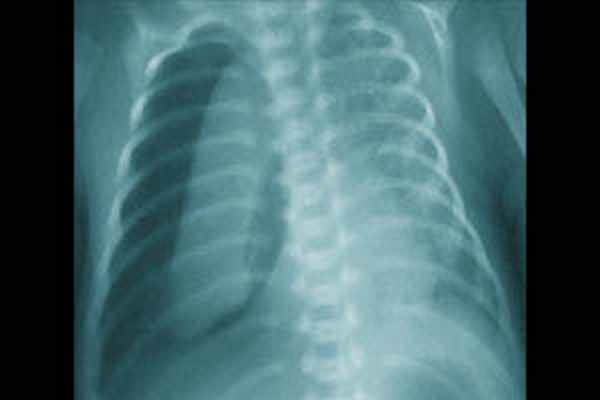

- Рентгенография ОГК. На рентгенограмме неонатолог обнаруживает просветление по периферическим отделам грудной клетки и спадение (коллапс) легкого. При этом средостение, как правило, смещено в здоровую сторону. Рентгенологическое исследование также применяется для диагностики пневмоперикарда.

Диагноз ИЛЭ ставится на основании клинических, рентгенологических и лабораторных данных. Иногда ИЛЭ диагностируется после дренирования пневмоторакса и расправления пострадавшего легкого. В большинстве случаев, выявлению ИЛЭ предшествует ухудшение состояния ребенка, снижение оксигенации, необходимость увеличения параметров ИВЛ, десинхронизация с аппаратной вентиляцией, тенденция к артериальной гипотензии. При объективном осмотре у ребенка могут наблюдаться вздутие грудной клетки, крепитирующие хрипы на стороне поражения. Лабораторно выявляются гиперкапния, гипоксемия и ацидоз. Классическая рентгенография грудной клетки в прямой проекции лежа позволяет четко диагностировать ИЛЭ, которая проявляется в двух основных формах: линейной и кистозноподобной. Часто эти две формы выявляются вместе. Линейная ИЛЭ визуализируется как неразветвленные тени длиной от 3 до 8 мм, ширина их редко превышает 2мм. Кистозноподобная форма представляет собой округлые, иногда овальные, тени от 1 до 4 мм в диаметре. Иногда данная рентгенологическая картина ошибочно интерпретируется как нормально аэрированное легкое, окруженное экссудатом, как при аспирационном синдроме или отеке легких. Линейную форму необходимо дифференцировать от «воздушных бронхограмм» при РДС. «Воздушные бронхограммы» представляют собой протяжённые разветвлённые тени, напоминающие трахеобронхиальное дерево, постепенно уменьшающиеся и исчезающие к периферии. Линейная форма ИЛЭ видна в дистальных отделах лёгких, в стороне от бронхов и не имеет ответвлений.

Симптомы пневмоторакса у новорожденных

Неадекватная вентиляция приводит к дыхательной недостаточности. Кожа новорожденного приобретает синюшный оттенок в области носогубного треугольника и кончиков пальцев, при нарастании гипоксии формируется тотальный цианоз. При массивном пневмотораксе пораженная сторона грудной клетки выбухает, отмечается заметная асимметрия. Возникают сердечно-сосудистые нарушения: тахикардия, артериальная гипотония.